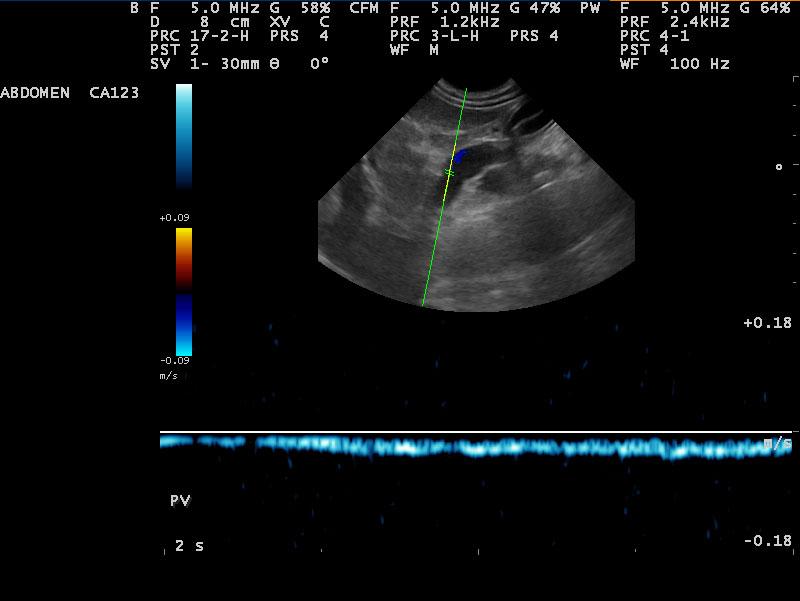

Diffuse nodular liver disease and microhepatica. The portal vein can be followed completely to its branches, but it is very tortuous and with the ascites that is seen, might be indicative of portal hypertension. This is typical cirrhosis with possible portal vein branch hypoplasia-microvascular dysplasia. The bile acids are likely very high and the clinical signs are owing to hyperammonemia. There are secondary shunts as well demonstrated by the tortuous vessels especially in the area of the pancreas where there is pancreatic edema. The lobe portal vein velocities support portal vein hypertension.